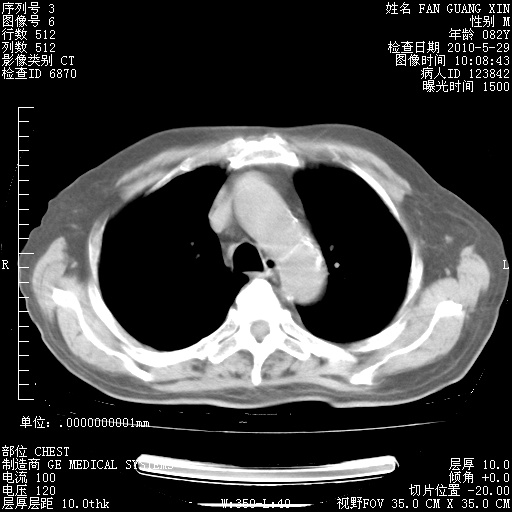

再治疗10天后的肺部CT